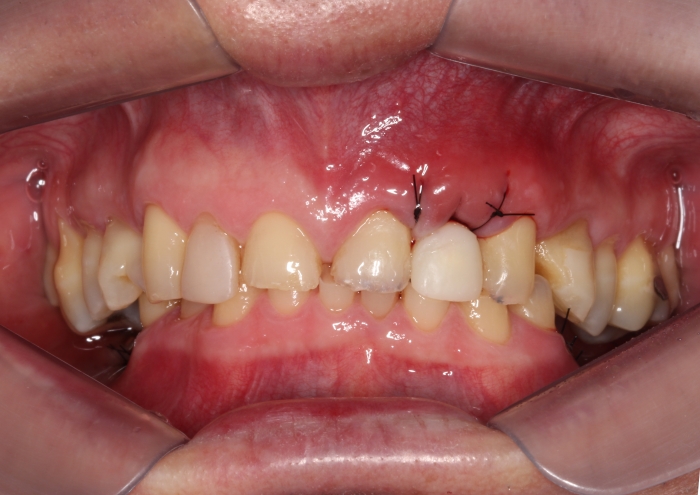

Imagem inicial em 2014

Sorriso inicial, em 2014